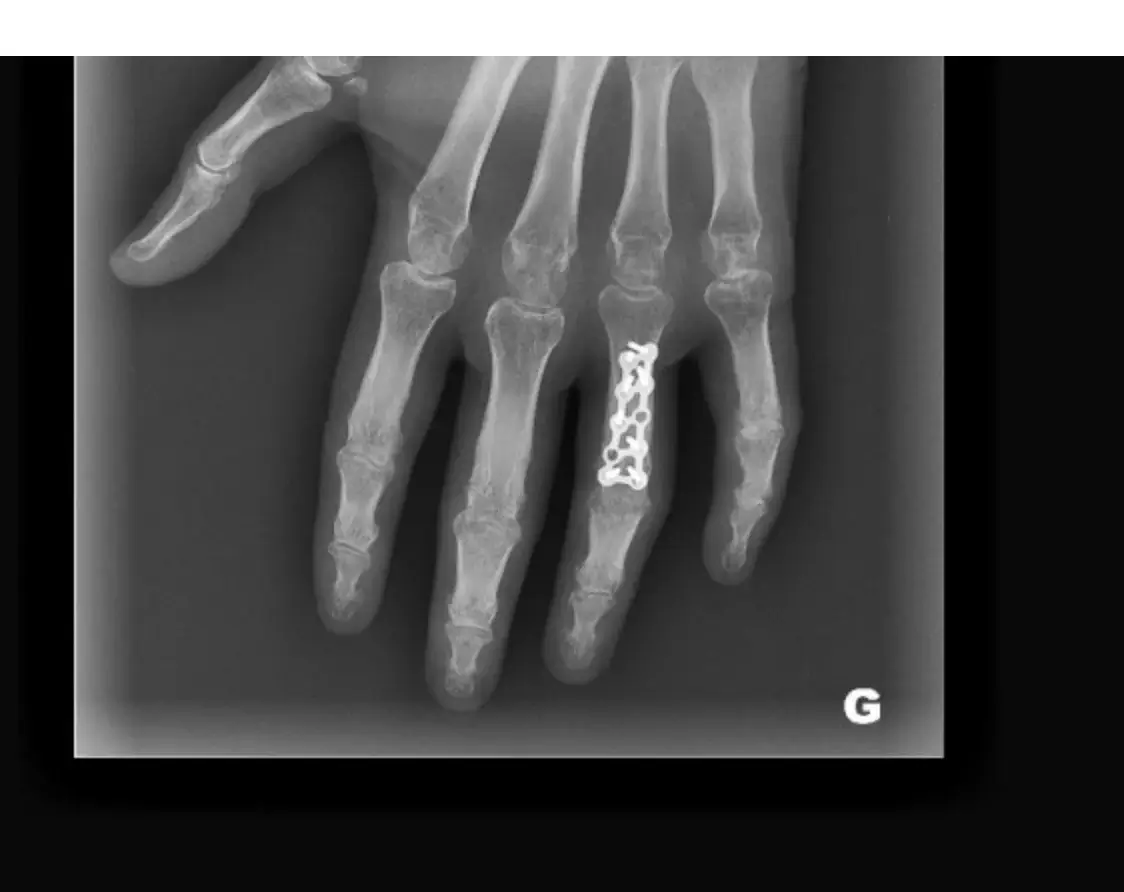

- fractures